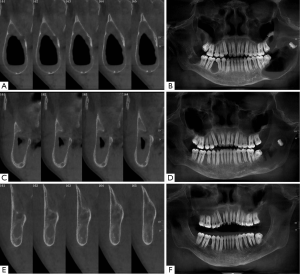

In addition, the radiographic results showed that the new drainage plug could help postoperative patients with large wounds return to near complete healing. After approximately 18 months of treatment with the new drainage plug, the cyst cavity healed completely with good new bone formation (Figure 6).